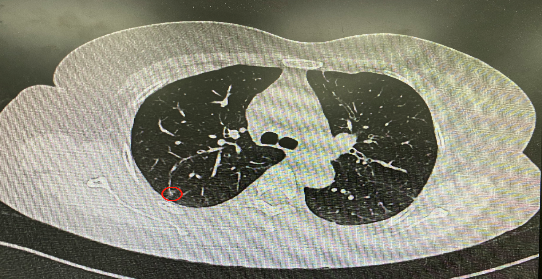

今年54歲的李女士(化名)7月初突然出現(xiàn)右上部腹痛,起初并未在意,以為稍作休息就會(huì)好轉(zhuǎn),但疼痛卻并未消退,持續(xù)了一個(gè)星期。李女士實(shí)在難以忍受,才在家人陪伴下來(lái)到西安國(guó)際醫(yī)學(xué)中心醫(yī)院就診。胸外科二病區(qū)崔凱主任接診患者后,詳細(xì)詢問(wèn)病情并查閱檢查資料,經(jīng)胸部HRCT檢查,結(jié)果提示:右肺上葉后段混合密度結(jié)節(jié)影,考慮原位癌可能,即將患者收入胸腔外科二病區(qū)住院治療。

經(jīng)與患者家屬溝通,崔凱主任決定行外科手術(shù)治療。為達(dá)到精準(zhǔn)切除,術(shù)前需進(jìn)行肺小結(jié)節(jié)切除前定位。由于結(jié)節(jié)位于右肺上葉后段,傳統(tǒng)經(jīng)胸外穿刺術(shù)無(wú)法抵達(dá)病灶。崔凱主任與呼吸內(nèi)科一病區(qū)歐陽(yáng)海峰主任討論后,決定擬行LungPro全肺診療導(dǎo)航下染色定位。即術(shù)前通過(guò)Lung Pro導(dǎo)航規(guī)劃染色位置,經(jīng)Lung Pro實(shí)時(shí)引導(dǎo)支氣管鏡抵達(dá)既定位置,注入亞甲藍(lán)染色劑標(biāo)記結(jié)節(jié)位置。

使用術(shù)前規(guī)劃系統(tǒng)重建全肺3D模型,并于外科醫(yī)生討論染色位置,最終確定標(biāo)記染色點(diǎn)—右肺上葉后段b亞段(RB2b)。術(shù)中使用P290(4.9mm外徑)標(biāo)準(zhǔn)支氣管鏡,根據(jù)導(dǎo)航術(shù)前規(guī)劃路徑,Lung Pro實(shí)時(shí)導(dǎo)航下,GS鞘管進(jìn)入RB2b遠(yuǎn)端官腔外病灶并注射亞甲藍(lán)染色劑。